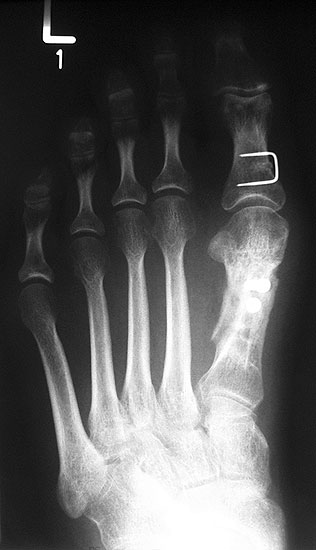

Die Röntgenaufnahmen (Abbildung 1) zeigen den Fuß einer 34 jährigen Patientin nach Exostosenabtragung. Der erhöhte intermetatarsale Winkel wurde durch eine alleinige Abtragung der Exostose nicht reduziert. Als weiterer Risikofaktor für ein Rezidiv liegt ein pathologischer Gelenkwinkel vor. Der intermetatarsale Winkel von 18 Grad kann durch eine basisnahe Osteotomie gut korrigiert werden. Da durch die gleichzeitige distale Korrektur des Gelenkflächenwinkels mithilfe einer Reverden-Green Osteotomie ein Längenverlust von ca. 2-4 mm einhergeht, bot sich als proximales Korrekturverfahren die basisnahe Open-wedge Osteotomie an, um bezüglich der Länge des Metatarsale I neutral zu bleiben (Abbildung 2). Die Kombination zweier verkürzender Verfahren (z.B. Lapidus und Reverden-Green) würden zu einem sehr kurzen ersten Strahl führen, mit dem Risiko einer Transfermetatarsalgie. Übersteigt die Verkürzung des Metatarsale I 2 mm, steigt das Risiko für die Entwicklung einer Transfermetatarsalgie deutlich an 8. Die durchgeführte Revision zeigt eine gute Stellung des 1. Strahls bei zentriert stehendem Gelenk.